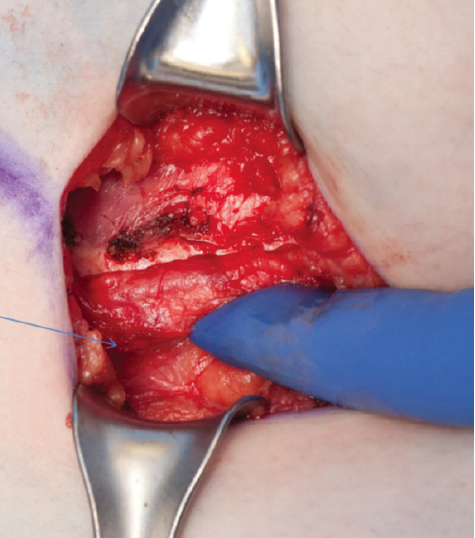

Imad Absah, MD; Youssef Ghazzawi, MD; Abdalla E. Zarroug, MD

<p class="p1">A 16-year-old girl presented with a history of chronic epigastric and right upper quadrant abdominal pain for years. The pain was sharp and was not associated with nausea,...